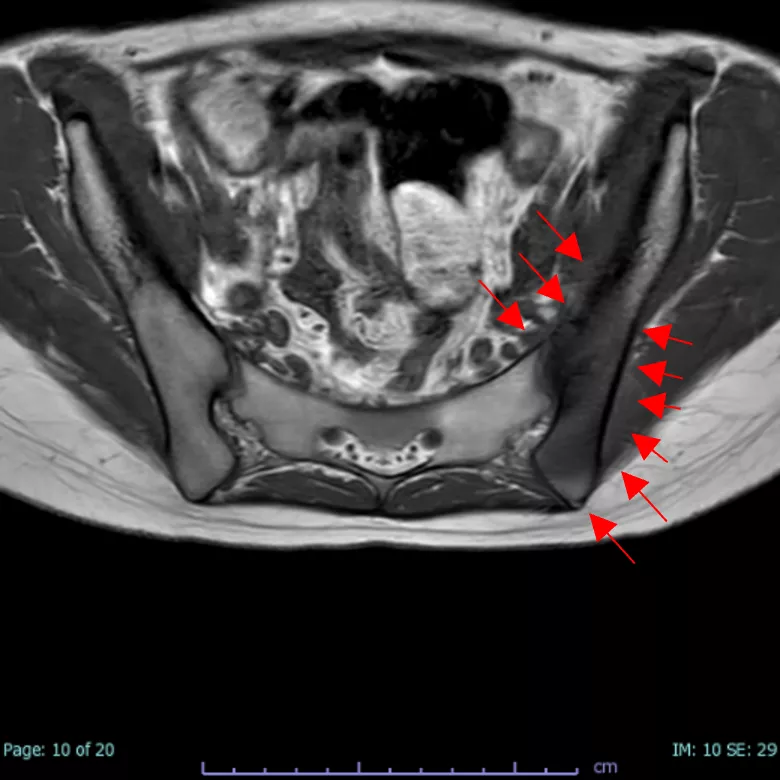

写真2

仙腸関節のMRI画像 腸骨のみに病変あり